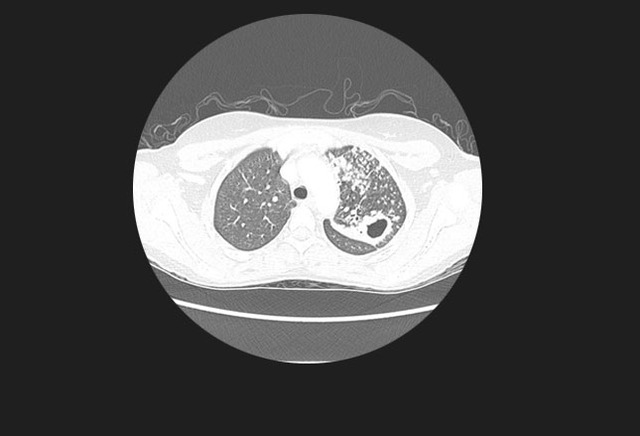

图2. 无数的肺部小结节,与粟粒型肺结核表现一致

初次感染结核常为隐匿性经过,少数患者可能会有明显的血液播散,导致粟粒型肺结核。

影像学特征包括斑片状或肺叶的实变、空洞(继发性肺结核的典型表现)、纵隔淋巴结肿大和胸腔积液。继发性肺结核常侵犯上叶尖后段及下叶背段。代表着血行播散的粟粒型肺结核并不常见,但预后不佳。